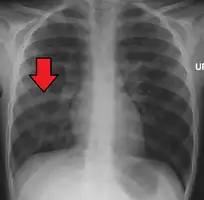

A chest X-ray showing a very prominent wedge-shape area of airspace consolidation in the right lung characteristic of acute bacterial lobar pneumonia

A chest radiograph is frequently used in diagnosis.[20] In people with mild disease, imaging is needed only in those with potential complications, those not having improved with treatment, or those in which the cause is uncertain.[20][60] If a person is sufficiently sick to require hospitalization, a chest radiograph is recommended.[60] Findings do not always match the severity of disease and do not reliably separate between bacterial infection and viral infection.[20]

X-ray presentations of pneumonia may be classified as lobar pneumonia, bronchopneumonia, lobular pneumonia, and interstitial pneumonia.[66] Bacterial, community-acquired pneumonia classically show lung consolidation of one lung segmental lobe, which is known as lobar pneumonia.[34] However, findings may vary, and other patterns are common in other types of pneumonia.[34] Aspiration pneumonia may present with bilateral opacities primarily in the bases of the lungs and on the right side.[34] Radiographs of viral pneumonia may appear normal, appear hyper-inflated, have bilateral patchy areas, or present similar to bacterial pneumonia with lobar consolidation.[34] Radiologic findings may not be present in the early stages of the disease, especially in the presence of dehydration, or may be difficult to interpret in the obese or those with a history of lung disease.[21] Complications such as pleural effusion may also be found on chest radiographs. Laterolateral chest radiograph can increase the diagnostic accuracy of lung consolidation and pleural effusion.[33]